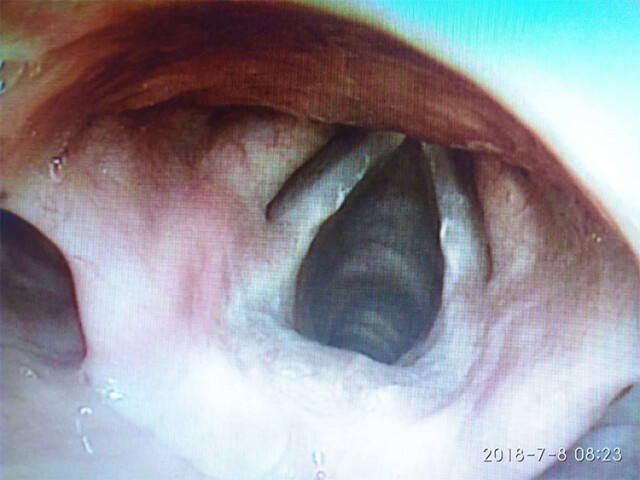

这个夏天因为世界杯的举行而激情四射,激情过后湖南省中医药研究院附属医院五官科迎来了一群特殊的患者——他们或声音嘶哑、或突然失声、或伴咽喉疼痛,虽表现各不相同,但是仔细询问病史,均是由熬夜看球所诱发。喉镜下示声带或水肿、或粘膜可见破损、或喉粘膜可见水肿。

声带位于喉腔中部,是人体重要的发声器官,其前为喉,后接气道,粘膜表面覆一层黏液,具有保护声带并通过润滑声带辅助声带振动发声,熬夜(kanqiu)、刺激性食物(xiaoye)、过度发声(hecai)、刺激性气体及粉尘(chouyan)等均会导致其分泌不足或增加其摩擦,从而引起局部的黏膜破损、水肿,导致声带炎。